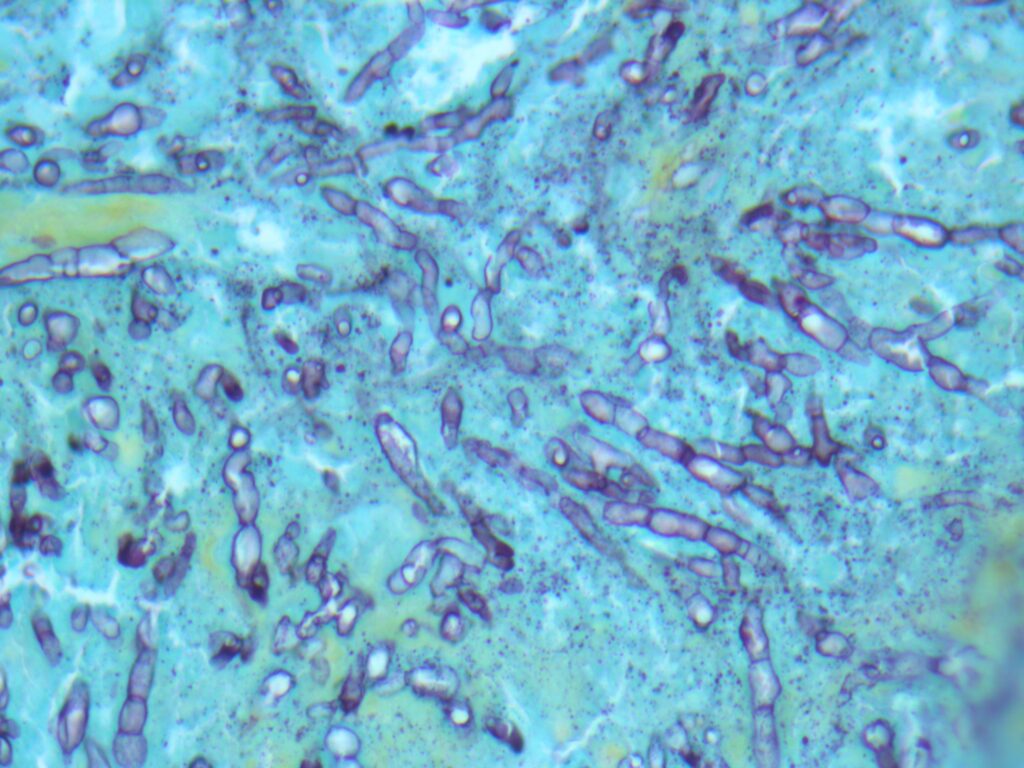

Histopathology: Evaluation using H&E and GMS staining revealed granulomatous inflammation (Fig 2), with septate, acutely branching fungal hyphae embedded in fibrinous material.

- Tape mount: Short septate hyphae (some thin, with dark pigment) with toruloid forms and abundant chlamydospores (Fig 4)